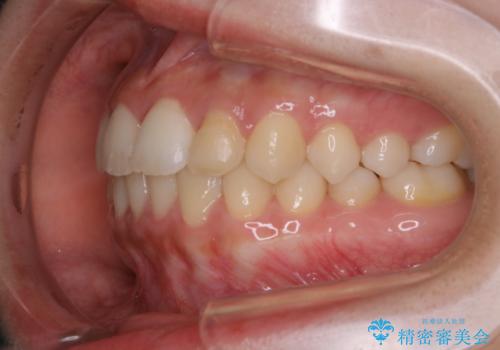

矯正治療終了後にPMTC(Professional Mechanical Tooth Cleaning)

- 矯正治療が終了したため、クリーニングでもきれいにしたいとのことでした。PMTC60分コースを行いました。

矯正治療が終わり、せっかくきれいになった歯並びも、虫歯・歯周病などになってしまっては元も子もありません。

矯正治療やセラミックなどによる被せ物の治療終了のタイミングではクリーニングを行い、汚れや着色の除去、歯と歯の間・歯と歯肉との境目などのケアをしっかりすることをおすすめしています。